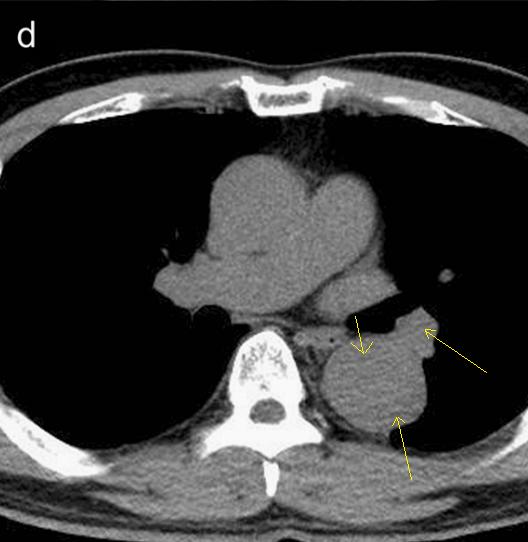

仔细一看,主动脉里面有线样阴影!并且,线样阴影两边的密度一高一低!

图8

增强CT一看,主动脉夹层,密度相对高的是流动的血液!

图9